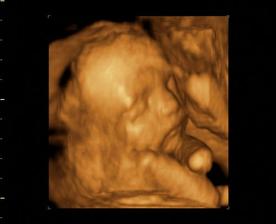

Nasa fazulka-Nellynka

Veď ja meškááám! A nie málo!!! Schytila som babytest a bežala som na WC. A hádajte! Sú tam. Dve ||. KRÁSNE, TUČNÉ A MOJE!!! Bolo to 9.9. 2oo7.